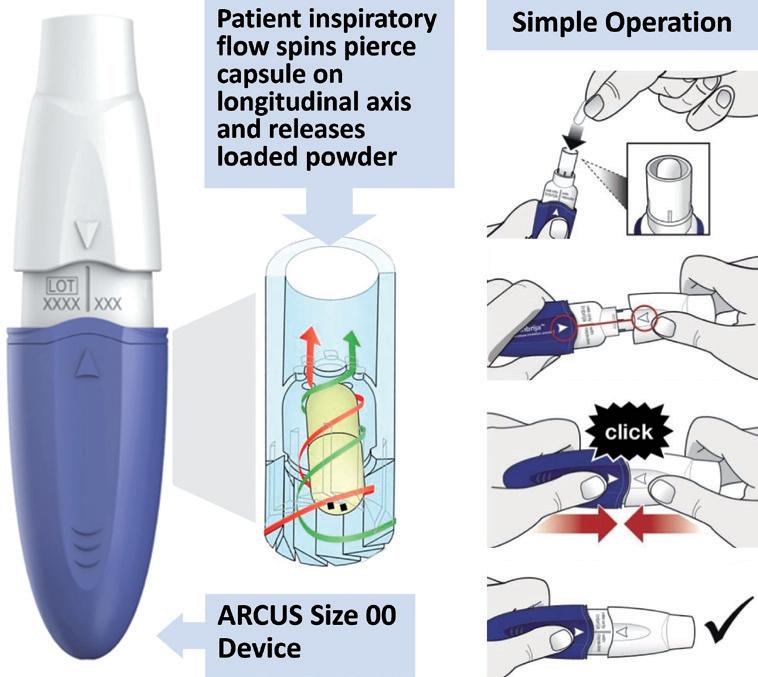

ARCUS®: a Commercialised Technology Enabling High-Dose, Highly Respirable Powders

Alan Watts, Director of Innovation & Partnerships for Orally Inhaled Products

Catalent

Michael Tauber, Senior Director of Pharmaceutical Development

Acorda Therapeutics